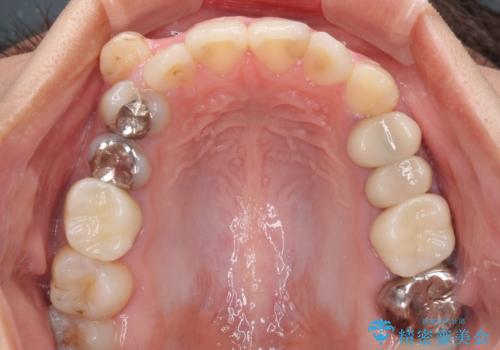

結婚式前に目立つ銀歯をセラミックに

折角セラミッククラウンを装着するので、根管治療を行った後に補綴治療を行うこととしました。

他にも目立つ銀歯がありましたが、最も気にしている2本を優先して行うこととしました。

結婚式前にはクリーニングやホワイトニングを行い、その後他の歯を治療していく予定です。